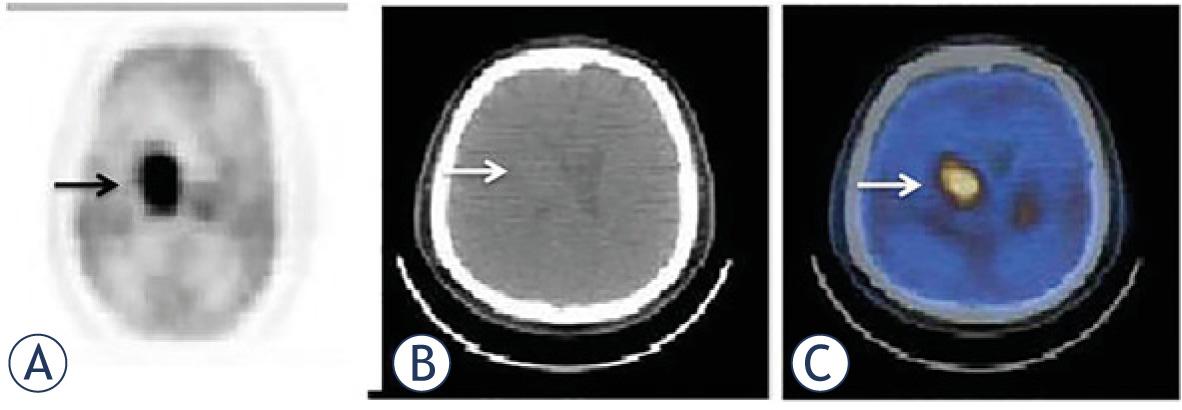

Primary testicular lymphoma is mostly DLBC and accounts for up to 5% of testicular masses presenting with painless swelling. It is usually aggressive with spread into the nervous system.12 Asymmetrical intense FDG uptake is usually seen. Over half of our patients either recurred or metastasized mainly into the nervous system. The disease showed its wicked face during its fatal cruise. Primary CNS lymphomas account for approximately 6.6–15.4% of CNS neoplasms and are usually of DLBC type.13 Although MRI is the choice of imaging modality due to the fact that presence of high physiologic FDG activity in cerebral cortex may hinder the visualization of lesions, FDG-PET/ CT is now well established in the evaluation of CNS lymphomas with a pattern of intense FDG uptake. All our cases of primary CNS lymphoma were DLBC type with high FDG accumulations. The disease was very aggressive and fatal (Figure 4). All the cases recurred and 5/7 (71%) of the patients died during the follow-up. Orbital lymphomas constitute approximately 8% of extranodal disease. Marginal zone (MALT) lymphoma is the most frequent variant, DLBC is the second most common type.14 They are invariably FDG-avid ranging from moderate to high uptake.14 4/11 (36%) of our CNS lymphomas were primary orbital lymphoma and mostly MALT showing mild to moderate uptake. Their prognosis was indisputably very well contrary to the intracranial DLBC subtype.

61-year old female patient was diagnosed with primary CNS lymphoma of DLBC type. There was a mass in right periventricular region adjacent to right thalamus on transaxial PET (A), CT (B) and fusion (C) images (arrows). She was in serious risk because of her high metabolic tumor parameters (SUVmax: 35, SUVmean: 25, MTV: 425 cm3, TLG: 2543) and died of the disease 11 months after the diagnosis.